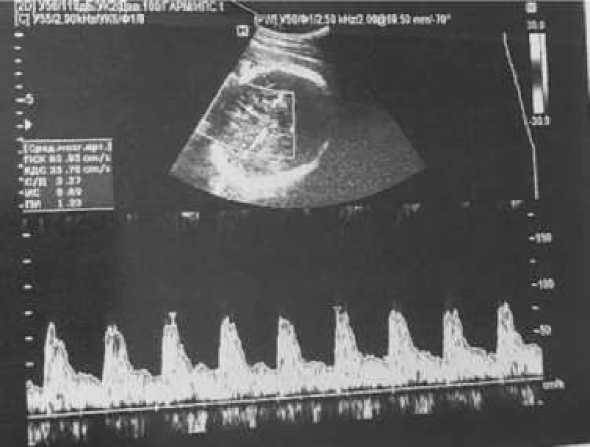

На 32-й неделе беременности при повторной явке в женскую консультацию, учитывая отягощенный акушерско-гинекологический анамнез, было выполнено антенатальное ультразвуковое исследование, на котором было выявлено головное предлежание плода, ВПС плода по типу тетрады Фалло, кардиомегалия (гипертрофия миокарда обоих желудочков, умеренное количество жидкости в полости перикарда), двусторонний гидроторакс, асцит. Ультразвуковые признаки неиммунной водянки плода (рис. 3).

Рис. 3. Фотофиксация изображений АУО плода на 32-й неделе беременности

По достижении срока беременности 33 недели и 3 дня была проведена телемедицинская консультация с ФГБУ «Национальный медицинский исследовательский центр акушерства, гинекологии и перинатологии им. академика В.И. Кулакова». В ходе телемедицинской консультации был подтвержден ВПС: двойное отхождение магистральных сосудов от правого желудочка по типу тетрады Фалло (субаортальный дефект межжелудочковой перегородки (ДМЖП) с открытым овальным окном (ООО), подклапанный стеноз легочной артерии). Отмечена положительная динамика течения неиммунной водянки плода: гидроперикард незначительный, остаточные явления асцита, гепатомегалия плода (вертикальный размер печени 67 мм). Фетоплацентарный и маточно-плацентарный кровотоки в пределах нормы. Учитывая данные ультразвукового исследования и данные анамнеза, имеется высокая вероятность внутриутробного инфицирования (парвовирусом В-19) с развитием неиммунной водянки плода вследствие анемии. Кроме того, при оценке скорости кровотока средней мозговой артерии (СМА) плода выявлена высокая вероятность анемии средней степени тяжести. Отмечается сохраняющееся многоводие на уровне значений индекса амниотической жидкости 27 см. Рекомендовано: госпитализация в акушерский стационар III уровня, дообследование, динамическое наблюдение, повторное обследование пациентки на вирусные инфекции (проведение ИФА), включая парвовирус В-19, цитомегаловирус, вирус герпеса, вирус Эпштейна – Барр, антитела к новой коронавирусной инфекции, повторное микробиологическое исследование влагалища и повторная консультация через 7 дней или по показаниям (в случае ухудшения состояния плода).

В связи с вышеперечисленным больная была госпитализирована в Клинический перинатальный центр Саратовской области. На этапе госпитализации было проведено полное клинико-лабораторное обследование, подготовка сурфактантной системы плода дексаметазоном. Ежедневный динамический контроль скорости кровотока по СМА плода и кардиотокографии с целью мониторинга состояния внутриутробного развития плода. При дальнейшем клинико-лабораторном обследовании были вновь выявлены антитела к капсоидному антигену вируса Эпштейна – Барр (в количестве 54,56 копии) и антитела к парвовирусу

В-19 (в количестве 2,34 копии). На 34-й неделе беременности при повторном АУО (рис. 4) наблюдалось продольное положение плода в головном предлежании. При бактериальном исследовании из цервикального канала были обнаружены 103 лактобактерии (что подтвердило нормальную микрофлору влагалища).